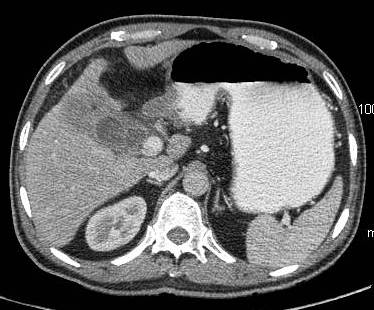

Common patterns of carcinoma gallbladder

Three patterns have been described on ultrasonography (US). The gallbladder fossa is replaced by a heterogeneous mass (figure 1) with internal areas of necrosis; or there may be diffuse, irregular, and asymmetrical wall thickening (Figure 2); or less commonly, a polypoidal, fungating intra-luminal mass is seen. Correct preoperative diagnosis has improved considerably with the use of newer imaging techniques [6-8]. Majority of cases when diagnosed, are no longer resectable (Figure 3) [9-11].

Figure 3: large polypoidal fungating gallbladder mass with gross invasion of liver parenchyma. Hepato-duodenal ligament invaded. Left lobe shows discrete secondaries.